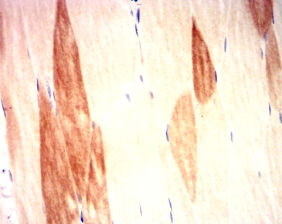

IHC    1/200 - 1/1000